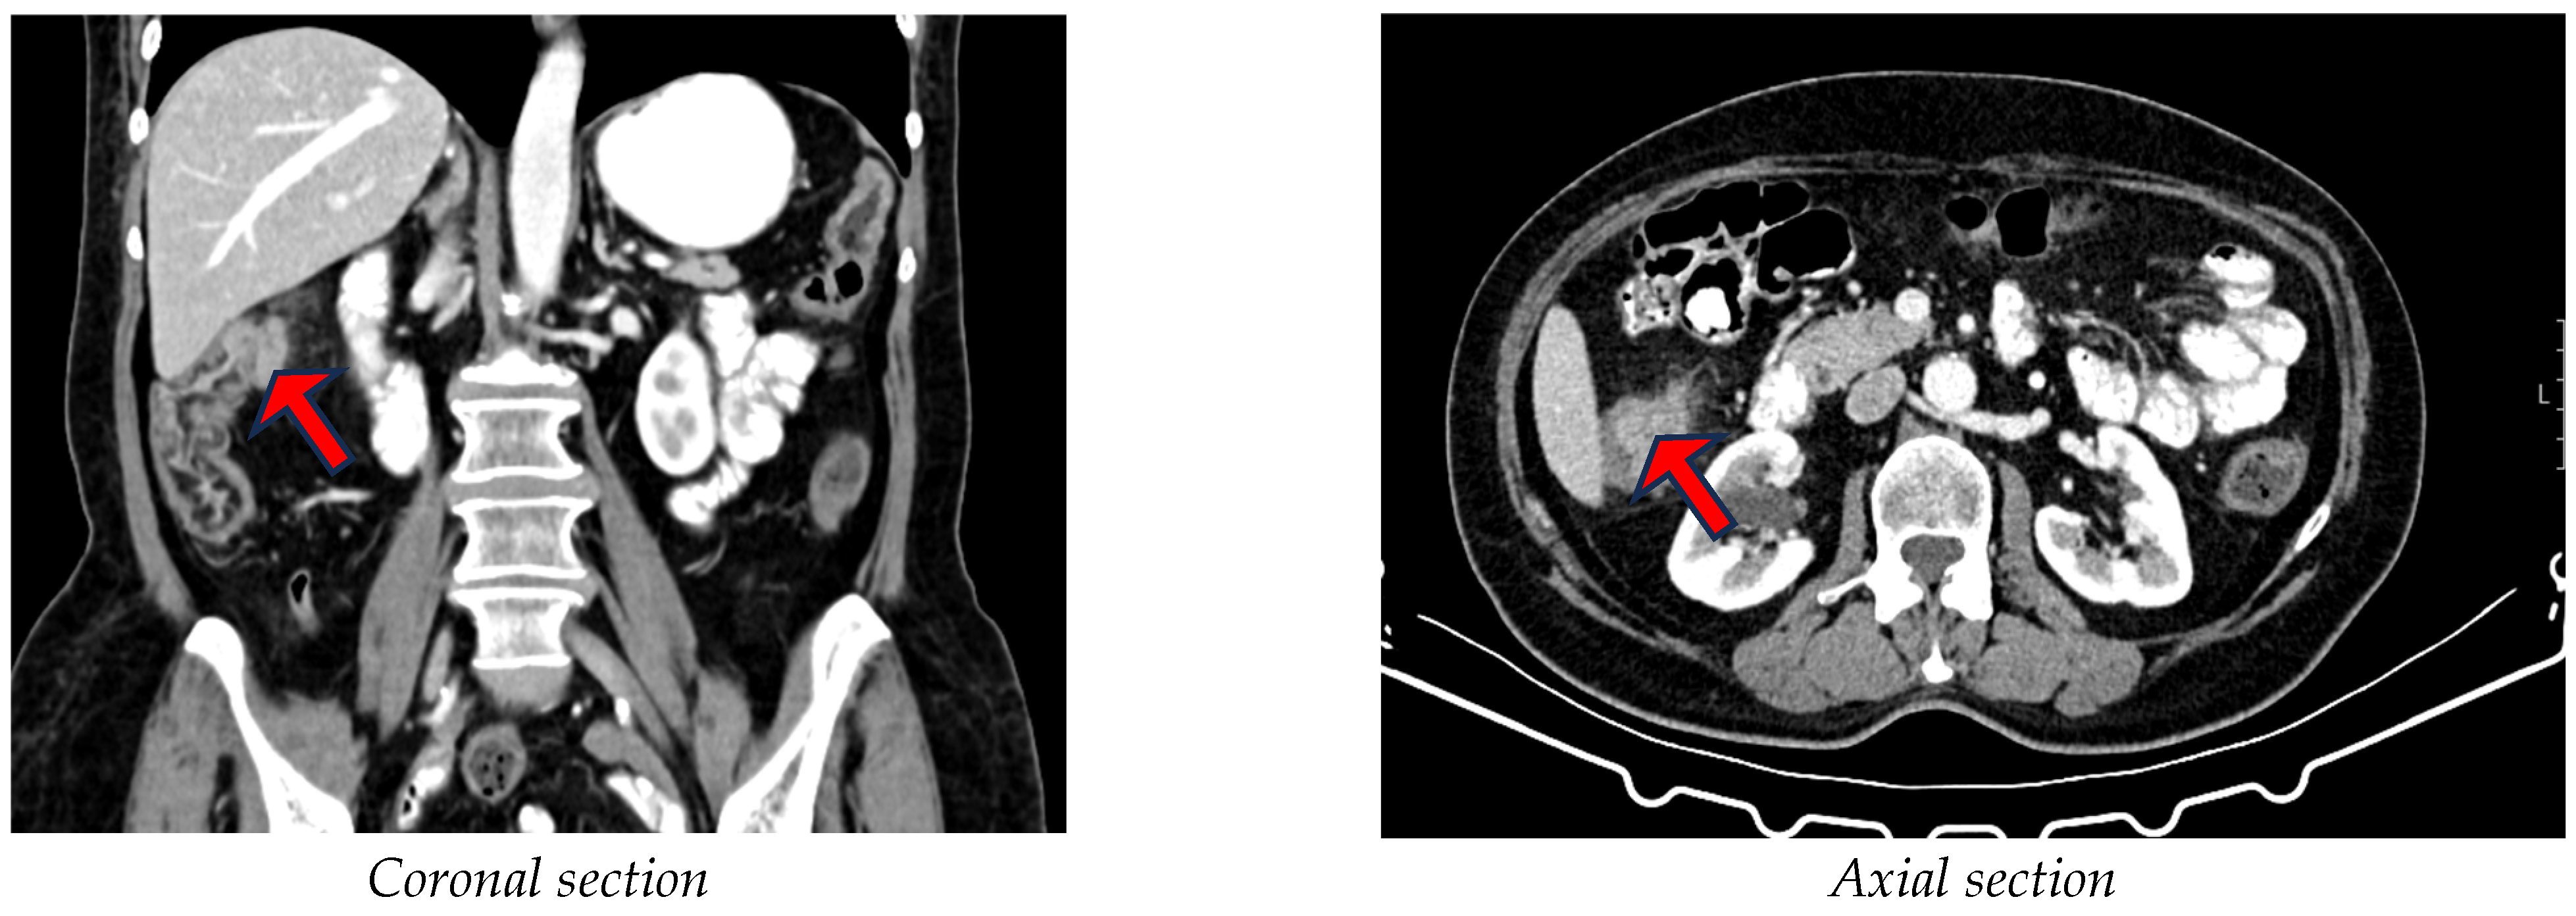

3.4. Radiological Parameters